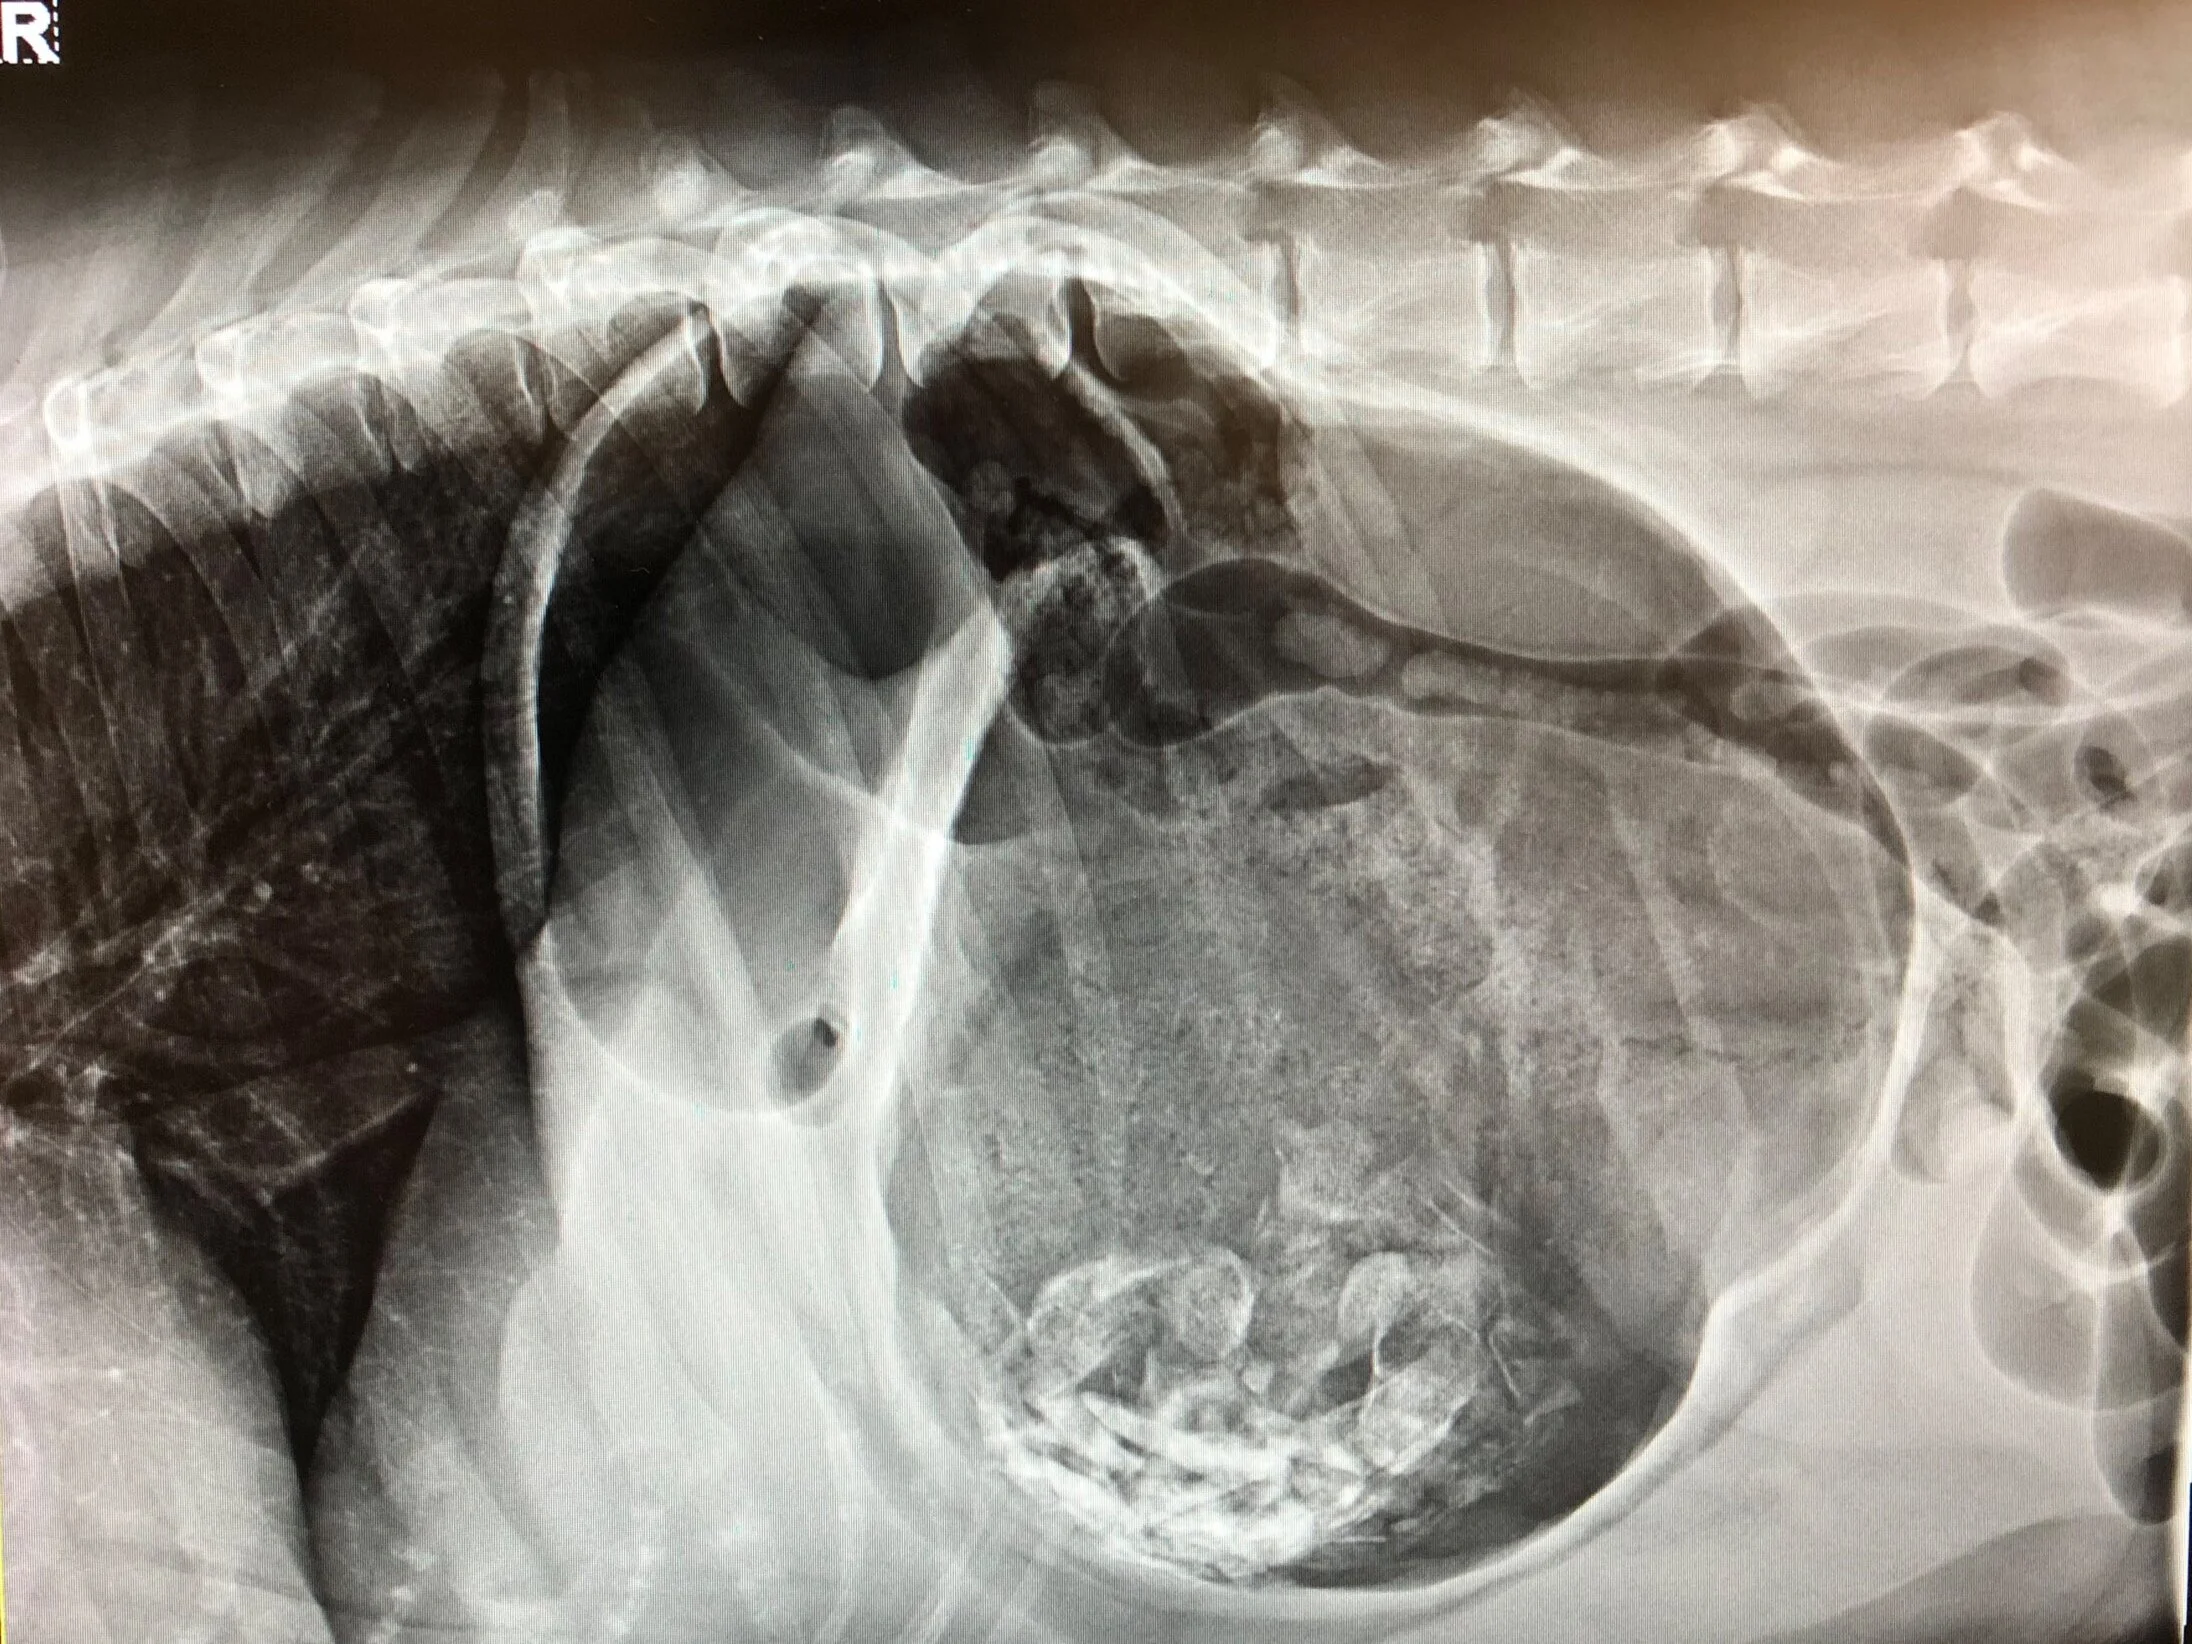

Dog Gastric Dilatation Treatment . This is where a dog's stomach rapidly fills up with gas and rotates or flips over on itself, resulting in the blockage of both the entrance and exit of the stomach. Whether done as part of surgical treatment of a gdv episode, or prophylactically in dogs that are considered to be high risk, attachment of the. Treatment is by debridement and repair of the gastric wall defect, followed by continued intensive supportive care. Gastric dilation and volvulus (gdv) is an enlargement of the stomach associated with rotation on the mesenteric axis.

From www.diagnosticmindset.com

Gastric dilatation or gastric volvulus in the radiographs of dogs? Dog Gastric Dilatation Treatment Treatment is by debridement and repair of the gastric wall defect, followed by continued intensive supportive care. Whether done as part of surgical treatment of a gdv episode, or prophylactically in dogs that are considered to be high risk, attachment of the. Gastric dilation and volvulus (gdv) is an enlargement of the stomach associated with rotation on the mesenteric axis.. Dog Gastric Dilatation Treatment.